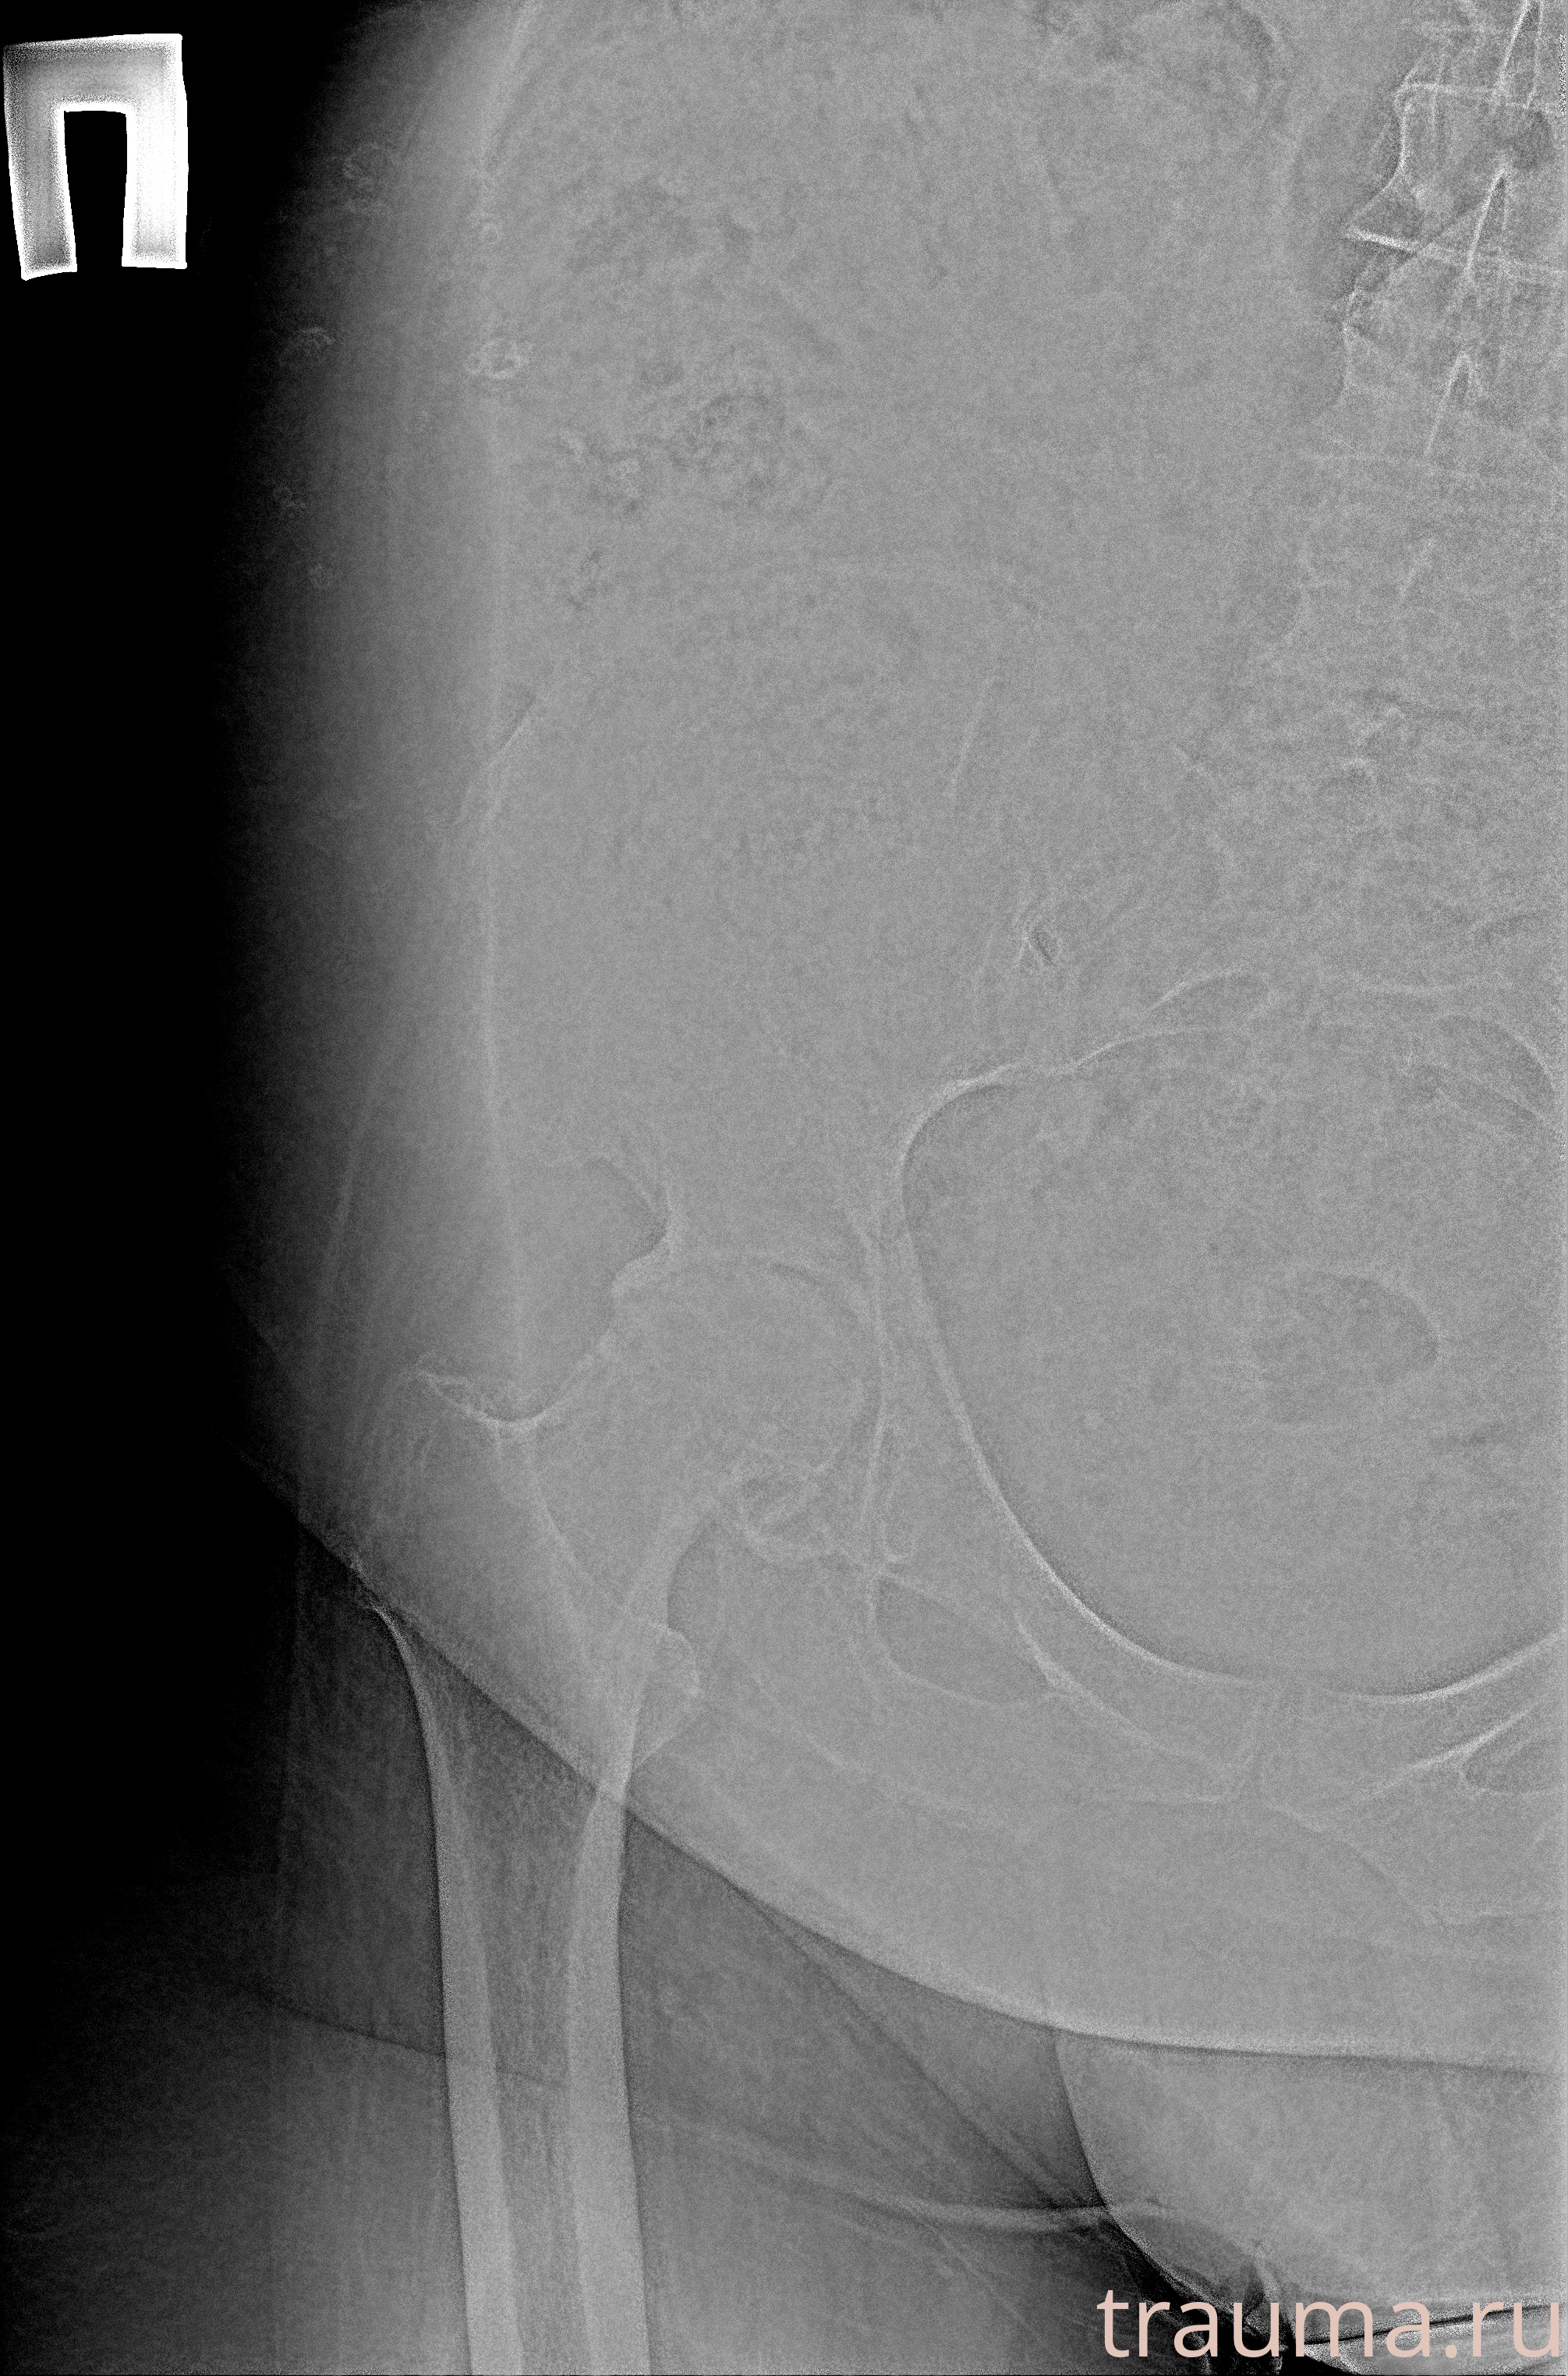

Рентген на дому: по вашему адресу приезжает врач-рентгенолог, травматолог-ортопед с мобильным рентгеновским аппаратом, проводит диагностику травмы или заболевания, делает необходимые рентгенограммы, дает рекомендации по дальнейшему лечению. Получить качественные снимки в домашних условиях возможно благодаря уникальной методике, разработанной МосРентген Центром для института  Склифосовского